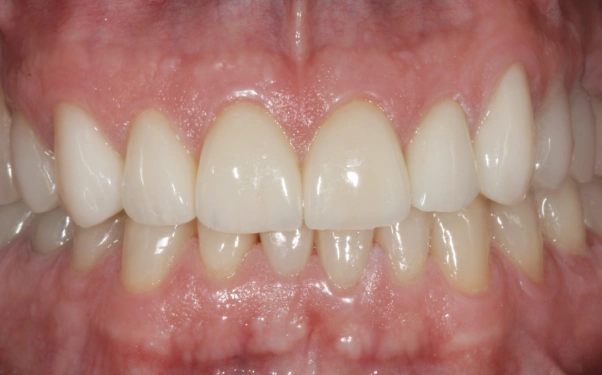

Depois

Foram confeccionadas facetas cerâmicas de dentes caninos a caninos superiores e inferiores, ponte fixa na região superior direita e coroas unitárias em dissilicato de lítio nos pré molares e molares.

Ao final do caso clínico, em 2017, indicamos uma placa miorrelaxante que foi confeccionada, no intuito de proteger os dentes de possíveis desgastes causados pela DTM (Distúrbio Temporo Mandibular).